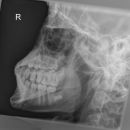

Unterkiefer nach Clementschitsch

Technik

• FDA: 1,15 m

• Ausgangsformat: 18/24 hoch

• mit Raster

• Röhrenkippung: 15° caudo-cranial

Lagerung

sitzt aufrecht und gerade mit dem Gesicht zum Stativ

Kopf gerade

Kinn stark anziehen lassen

Stirn dem Stativ anliegt

Mund maximal öffnen

Zentralstrahl

Im Winkel von mindestens 15° caudo-cranial okzipitomental. Längsstrahl verläuft durch die Medianebene. Querstrahl unterhalb des Occiputs auf Nasenwurzel. Achtung! Bei Röhrenkippung auf Zentrierung achten.

Anmerkung

Vollständige Darstellung des Unterkiefers und gute Beurteilung der Kiefergelenke. Bei Kiefergelenk Fragestellung:

1. Aufnahme mit geöffneten Mund

2. Aufnahme mit geschlossenem Mund

Qualitätskriterien

Übersichtliche Darstellung des gesamten Unterkiefers mit seitengleich gut einsehbaren Kiefergelenken